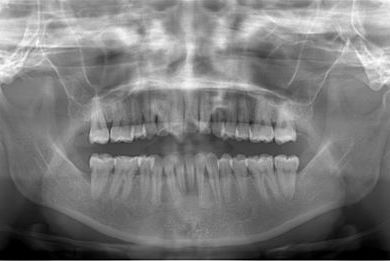

治療前

• 治療前

治療内容 ハイブリッドセラミックインレー3本

治療部位

7 6 7